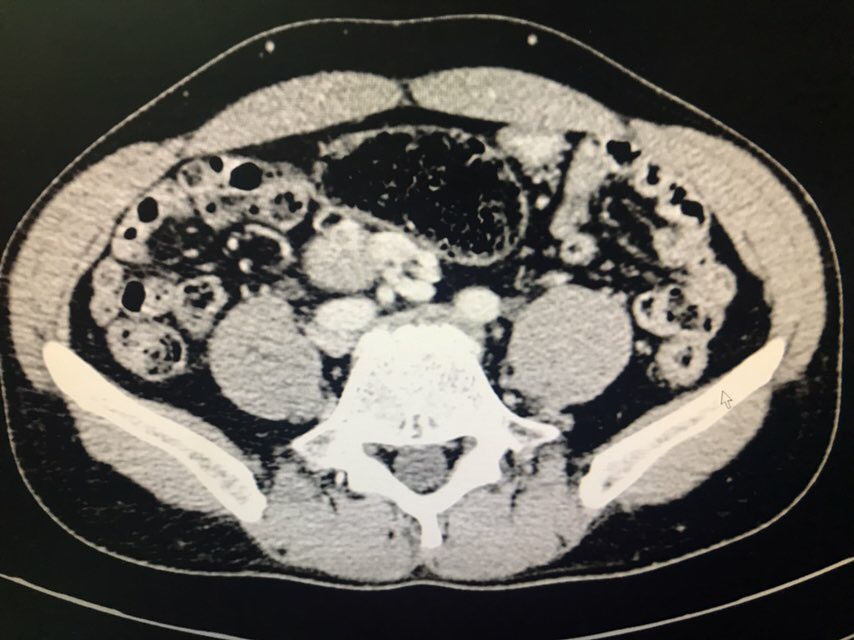

患者男性,43岁。主诉:发现盆腔占位1+月。现病史:患者1+月前于当地医院体检发现盆腔包块,于2018-08-28我院行泌尿系超声示:右侧髂窝实性占位伴钙化;2018-08-31我院行CT下腹部盆腔增强扫描示:下腹部及盆腔内多个软组织结节肿块影,肝右后叶上段囊肿;2018-09-07我院行病理检查示:盆腔肿瘤,倾向神经内分泌肿瘤,需行免疫组化染色检查;2018-09-07我院行膀胱超声示:超声引导下膀胱右侧盆腔内实性团块CNB。现患者为求手术治疗,于我院门诊就诊,以“盆腔肿瘤”收入我科。既往史无特殊。

查体:双侧腰部外形对称,皮肤无红肿,双肾区无叩痛,双肾下极未扪及,双输尿管行程区无压痛,膀胱区无隆起及压痛。双侧腹股沟区未扪及异常,无压痛;阴囊及尿道口未查。辅助检查:泌尿系超声(2018-08-28本院):右侧髂窝实性占位伴钙化;CT下腹部盆腔增强扫描(2018-08-31本院):下腹部及盆腔内多个软组织结节肿块影,肝右后叶上段囊肿;病理检查(2018-09-07本院):盆腔肿瘤,倾向神经内分泌肿瘤,需行免疫组化染色检查;膀胱超声(2018-09-07本院):超声引导下膀胱右侧盆腔内实性团块CNB。